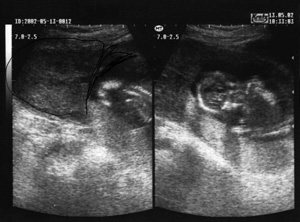

Εικόνα 3: Κύημα στο κατώτερο τμήμα της μήτρας Εικόνα 4: Αυξημένη διάταση μητριαίων αγγείων.

Ο συνδυασμός κοιλιακών και κολπικών υπερηχογραφημάτων που ακολούθησε, έθεσε τη διάγνωση της τραχηλικής κύησης. Η πρωιμότερη διάγνωση διέλαθε λόγω της μη συνδυασμένης εξέτασης κολπικού και κοιλιακού U/S. Επιθυμία της γυναίκας ήταν να συνεχίσει την κύηση και κατόπιν συνεννοήσεως και με άλλους συναδέλφους αποφασίστηκε η διατήρηση της κύησης υπό παρακολήθηση μέχρι του σημείου που θα ήταν δυνατή η γέννηση βιώσιμου εμβρύου. Ο έλεγχος ήταν κλινικοεργαστηριακός και προγεννητικός, υπερηχογραφικός καθώς και έλεγχος των μεγάλων αγγείων με Doppler με συμμετοχή και του τμήματος προγεννητικού ελέγχου του Νοσοκομείου "ΑΛΕΞΑΝΔΡΑ". Μετά πέντε έβδομάδες αποφασίστηκε ο τερματισμός της κύησης λόγω της μεγάλης διάτασης των μητριαίων αγγείων, την αύξηση της ροής τους, καθώς και την διάβρωσή τους από τον πλακούντα (εικ. 4).